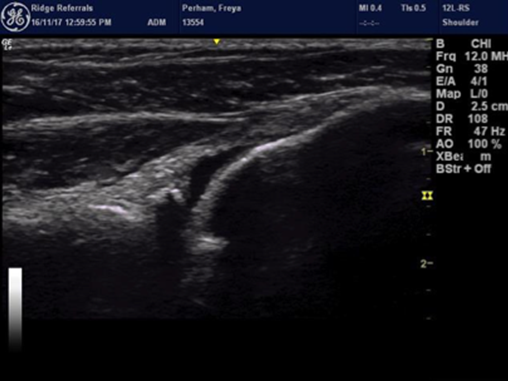

Once we know that it is the shoulder that is the cause of lameness and we have a fair idea of what is injured then we can think about confirming the diagnosis and so determine a treatment plan by imaging the structures. Traditionally X rays have been used to assess bony structures and in some cases where soft tissues have significantly degenerated and calcified, these changes may be seen on X rays. However in most cases plain X rays don’t help too much and so our protocol is to start with Computed Tomography (CT) in most cases. CT will allow us to see more detail in the shoulder and CT is very useful to rule out the elbow. Diagnostic ultrasound is then hugely beneficial in the shoulder as most of the structures on the side and front of the shoulder can be seen and typically this is done at the same time as the CT, assessing shoulder stability and so the integrity of ligaments under the same anaesthetic plays an important part as well.

- Biceps tendon injury is usually treated by rest, support and biologics in order to try and actually repair the tendon or by arthroscopic release if the tendon is irreparably damaged. Biceps tendon pain can also be a feature of Supraspinatus Insertionopathy which has similarities to Rotator Cuff Disease in people.

- Supraspinatus Insertionopathy is a poorly understood condition. The supraspinatus muscle attaches onto the humerus directly over the biceps insertion within the joint. In some patients damage to the attachment fails to heal and the attachment site degenerates, this can lead to mineralization within the attachment. The mineralization is the tip of the iceberg. This insertionopathy itself can be painful but it can also cause impingement of the biceps tendon. Treatment is by debriding the impingement or releasing the biceps tendon and using platelet right plasma (PRP) and sometimes stem cells to stimulate healing and reduce inflammation. These cases will typically take a long time to resolve and avoiding reinjury is vital.